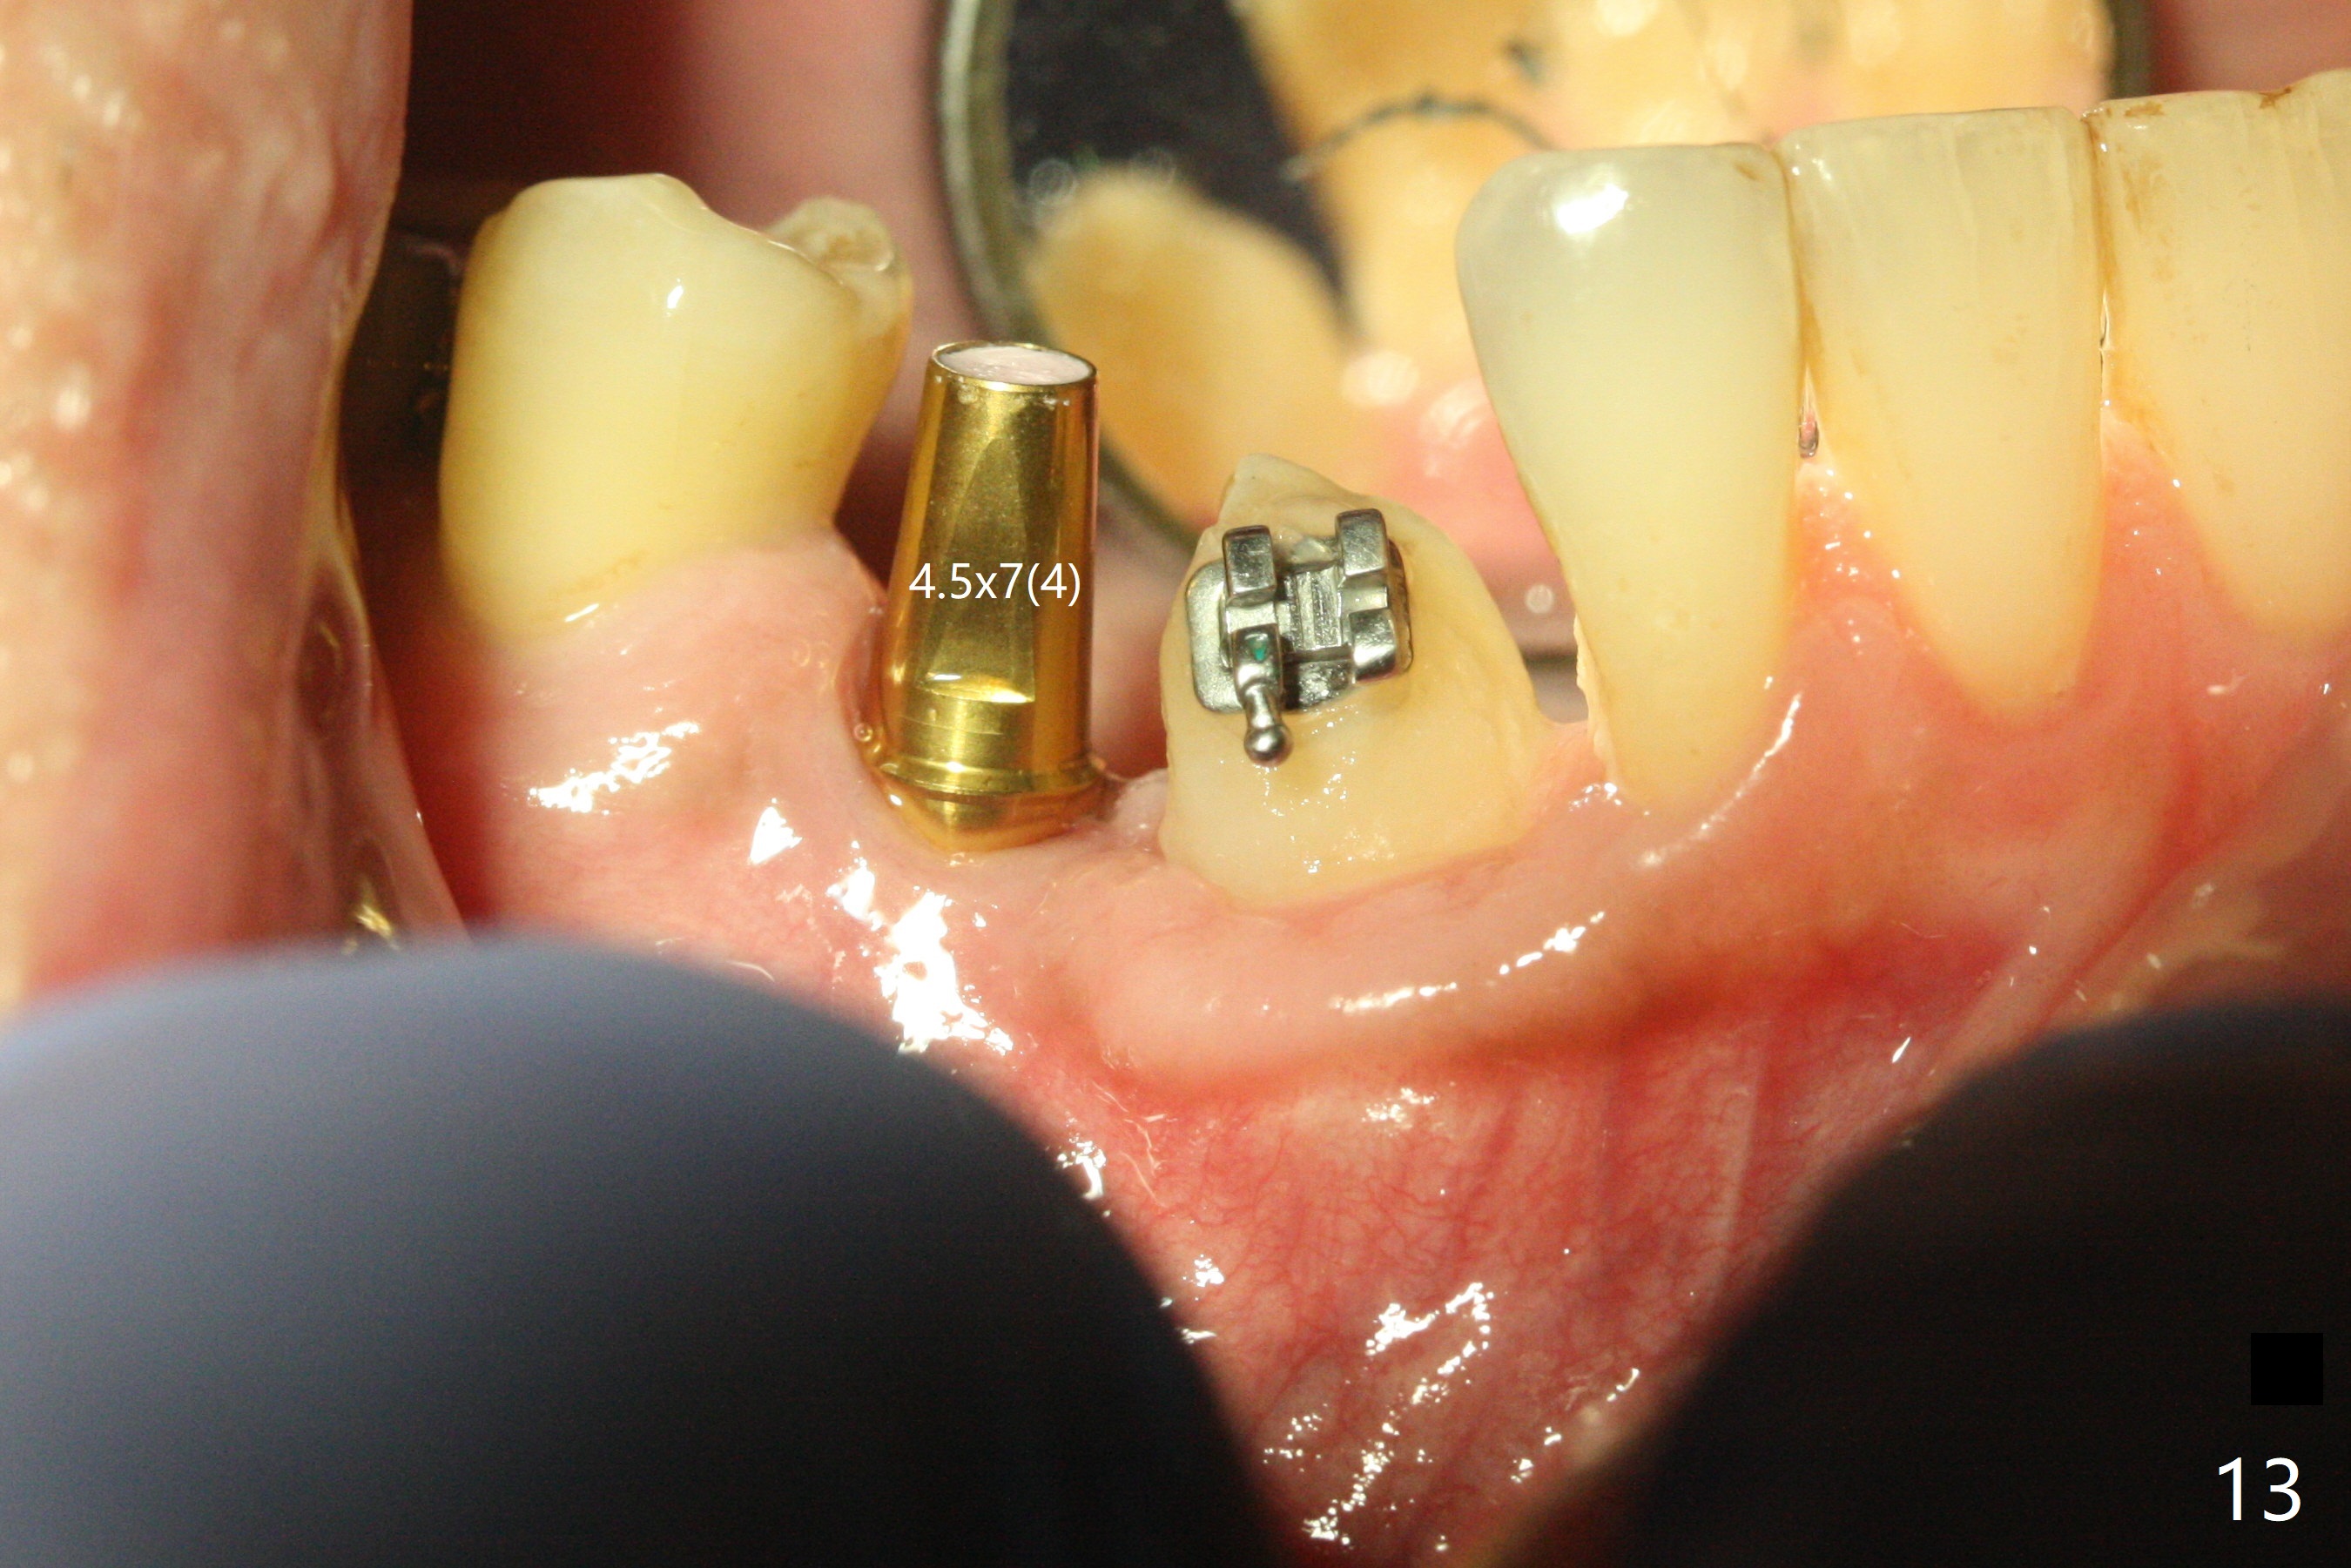

When the surgical guide for #28 is removed, the 4x13 mm implant is found to be superficial and buccal. Part of the buccal mucosa is nonkeratinized. After 1 mm deeper placement of the implant, CT confirms the buccal placement (Fig.1, as compared to design). In fact the guide was doubly checked for fitness prior to osteotomy, but grossly it seemed to be seated properly. The suspicion is related to the trimming at the site of #27 (Fig.2,3 (*), as compared to a mounted model in Fig.4,5 (arrowhead) and the model sent to lab for guide fabrication). The lab agrees to redesign the case. There is a narrow buccal band 1 week postop (Fig.6). The patient is a smoker. The implant was placed buccal (Fig.7, 1 month postop). A new 4x13 mm implant is placed on the top of the 1st line following 3x14.5 mm drill (Fig.8 (35 Ncm)). In fact the implant position is not changed much. Four months post banding (20 ss) and 2 months post 2nd implant placement, the tooth #27 is exposed for bracket; extrusion is initiated (Fig.9). In 3 weeks of retraction, the bracket is supragingival (Fig.10). The canine contacts the distal healing abutment with 2 months of retraction (Fig.11). It seems necessary to initiate lower bracket placement. There is no bone loss 4 months postop (Fig.12). A 4.5x7(4) mm abutment is placed (Fig.13) for a temporary crown as an anchor (Fig.14) to further extrude #27 with continuous inter-arch retraction (to reduce tension upon #26 with severe bone loss (Fig.12)). LR3 extrusion is incomplete, although there is an increase in bone distal to LR2 ~ 10 months of extrusion (Fig.15).